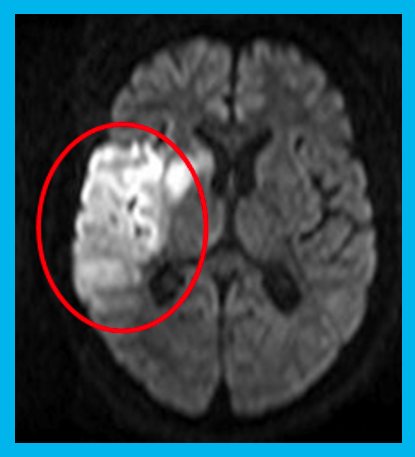

MRI検査

強力な磁場と電波を利用して体内の臓器や血管、神経などを詳細に描き出す検査です。放射線を使用しないため被ばくの心配がなく、安全に実施できます。脳や脊椎、関節、腹部など幅広い領域の精密検査が可能です。検査中は大きな音がしますが、リラックスして受けていただけるよう耳栓やヘッドホンを用意しています。

MRI検査には20~60分の時間を要します。脳内腫瘍をはじめ、感覚などの神経系、手足の関節、その他腫瘍が疑われる部位の軟部組織の描出を得意としています。また、造影剤を使用せずに脳や頸部の血管を描出することも可能です。さらに、CTに比べて脳梗塞の診断に優れており、より早期かつ正確な評価が可能です。

CTは脳出血の有無確認に優れ、検査時間が短く救急で有用ですが、発症直後の脳梗塞は変化が分かりにくい場合があります。MRIは早期の脳梗塞を白く明瞭に描出でき、病変の範囲や状態をより正確に評価できます